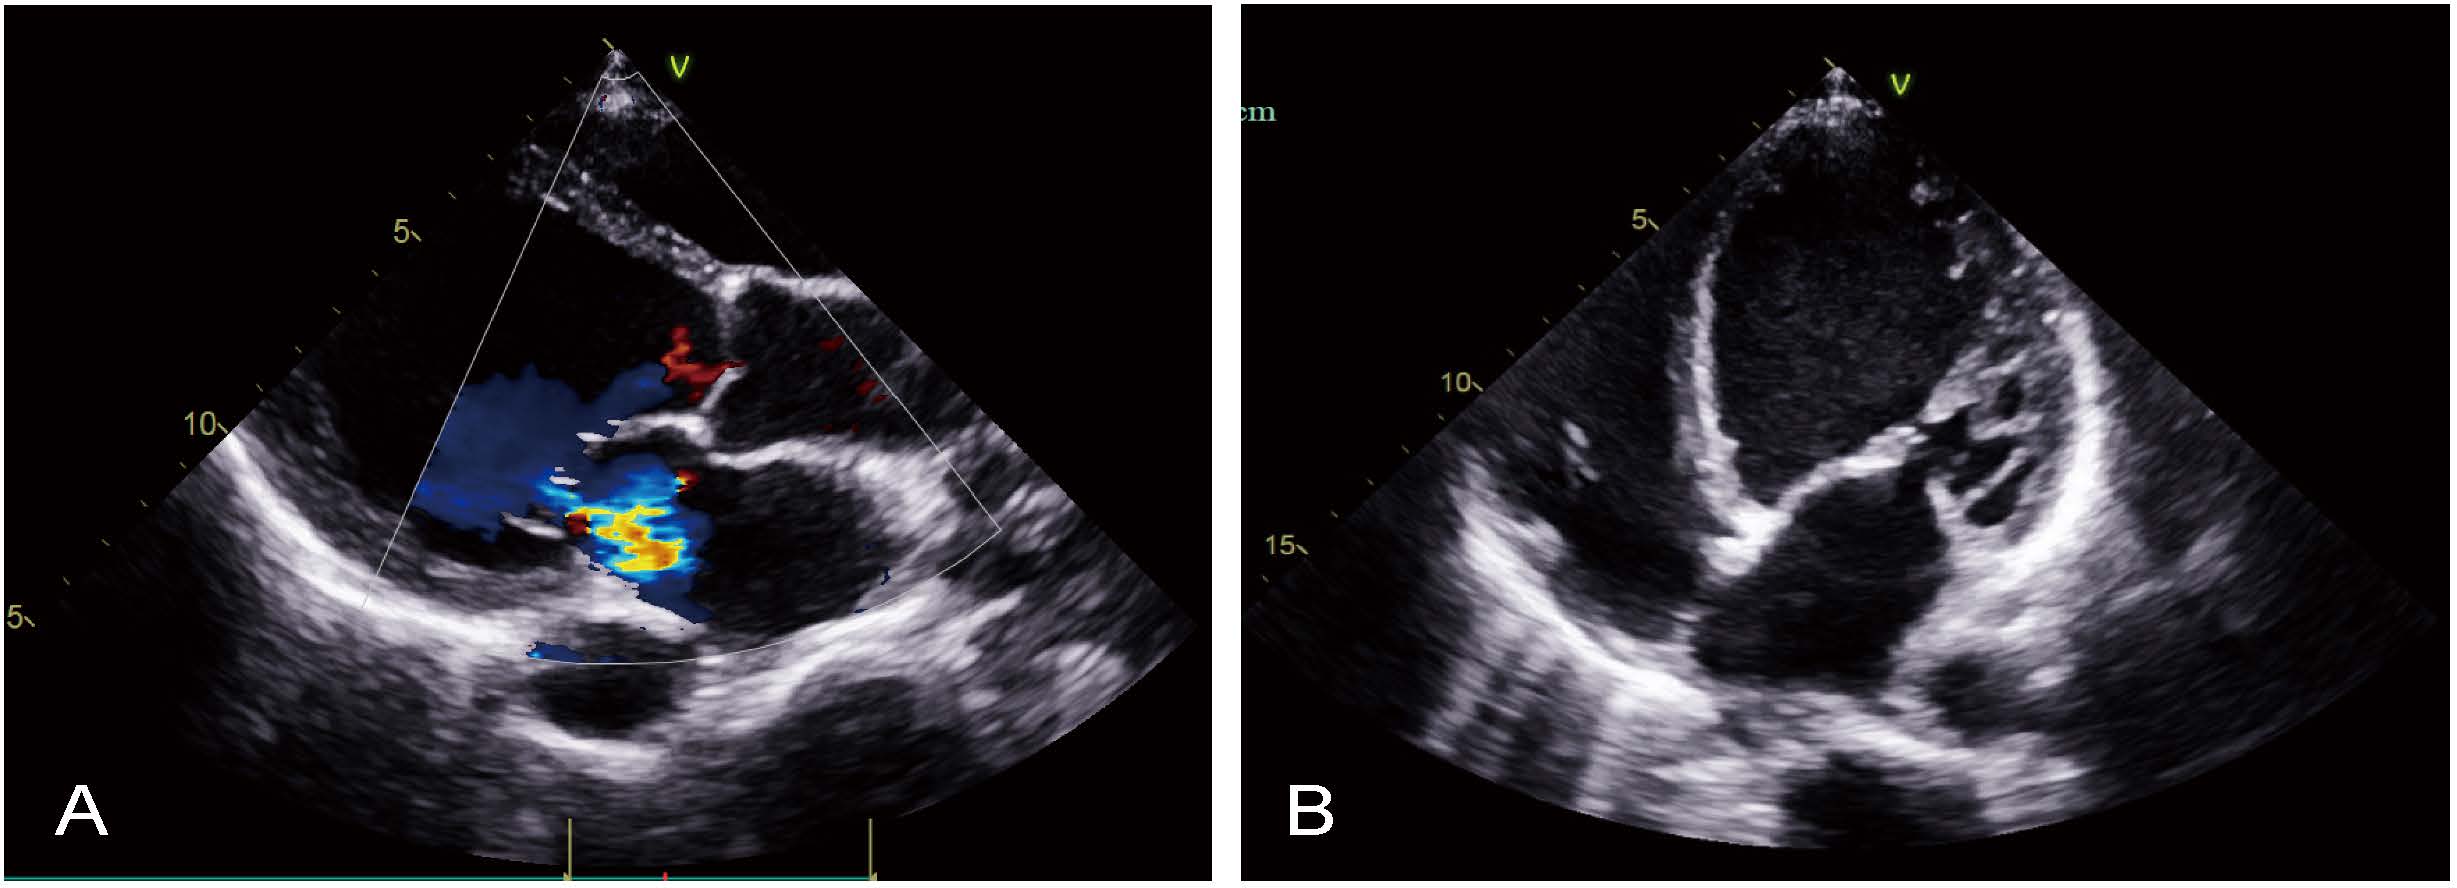

Electrocardiography revealed sinus tachycardia (115 beats/minute). Brain magnetic resonance imaging revealed no apparent abnormalities. Computed tomography (CT) of the lungs revealed signs of inflammation and emphysema (Fig. 1A). Pulmonary function tests revealed moderate to severe restrictive ventilatory impairment with moderate diffusion impairment. Echocardiography revealed mild mitral and tricuspid regurgitation, elevated pulmonary systolic pressure, significant enlargement of the left ventricle, diffuse hypokinesis of the left ventricular wall, and reduced left ventricular systolic function, with a left ventricular end-diastolic dimension of 63 mm and left ventricular ejection fraction (LVEF) of approximately 24% (Fig. 2A,B).

Fig. 2.

Preoperative transthoracic echocardiography. (A) Parasternal long-axis view. (B) Apical four-chamber view.